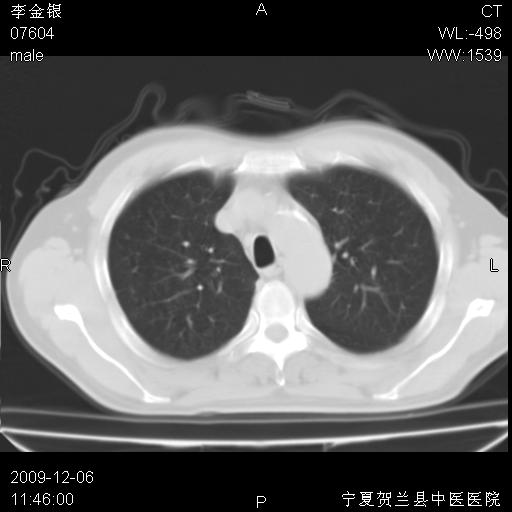

该病人 ,男,62岁,主因咳痰带血两天

考虑右肺中央型占位性病变并阻塞性肺炎.(右肺上叶支气管变窄),建议支纤镜检查.

支持右侧中央型肺癌伴上叶阻塞性炎症.

考虑右肺中心型肺癌伴阻塞性肺炎及右肺门淋巴结转移,建议纤维支气管镜进一步检查。

支气管壁明显增厚 管腔狭窄,腔静脉后多个淋巴肿大,结合年龄病史考虑右肺上叶中央型肺癌并阻塞性肺炎

右肺上叶后段支气管阻塞,右上肺门占位,相应肺段阻塞性肺炎,右肺门有淋巴结肿大。诊断右肺上叶中心型肺癌,阻塞性肺肺炎、右肺门淋巴结转移。

右上叶支气管狭窄,管壁增厚,远端斑片状软组织影,病灶邻近叶间裂,叶间裂无移位。

诊断右肺中央型肺癌。

那个片影应该大部分都是病灶,病灶沿肺段支气管分支生长,后段完全显示不清、闭塞。若为不张应该伴有叶裂的移位,若为炎症应有空气支气管征。